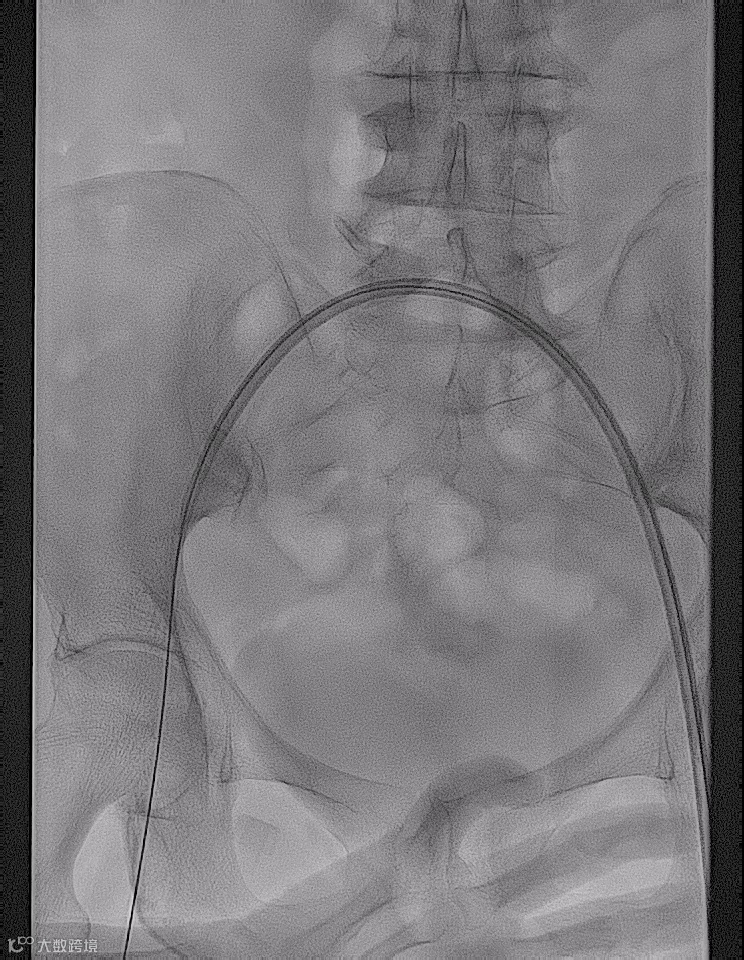

术前造影

手术过程